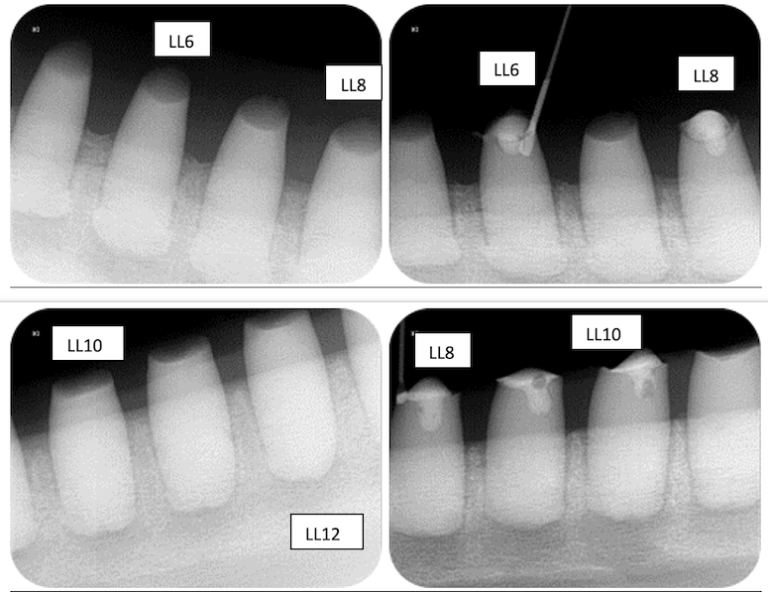

Johnny, on of the rescued dolphins released into the ocean on Sept. 3, 2022, required dental crowns as his teeth were damaged from living in captivity in highly chlorinated water. Photo: Dolphin Project.

Local news outlets reported that the three dolphins – Johnny, Rocky, and Rambo – were released to Banyuwedang Bay in Buleleng on Saturday. Johnny, the eldest of the three dolphins, was given dental crowns so he could feed himself in the ocean.

Johnny reportedly suffered in captivity at a hotel in Bali, along with Rocky and Rambo, in a pool that was heavily chlorinated, contributing to his injuries and dental problems.